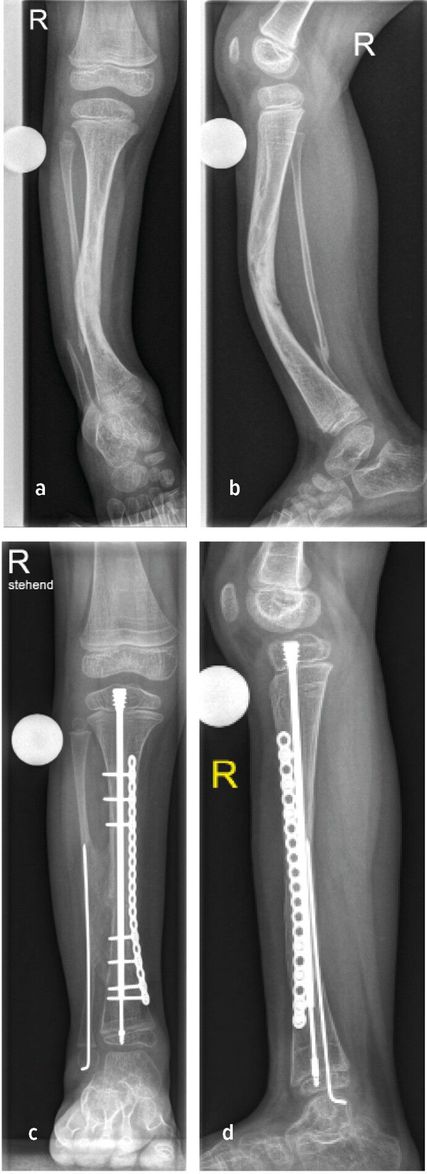

Im Falle eines anterolateralen Bowings richtet sich die Tibia nach vorne und außen. Differenzialdiagnostisch ist dabei im Schaftbereich an eine kongenitale Tibiapseudoarthrose (CPT) zu denken. Die Geburtenprävalenz der kongenitalen Tibiapseudoarthrose wird auf 1:140000 bis 1:250000 geschätzt. Neben dem kennzeichnenden Merkmal des anterolateralen Bowings können Frakturen der Tibia und/oder Fibula auftreten. Häufige Assoziationen vor allem mit Neurofibromatose Typ I sind beschrieben, jedoch ist das Auftreten einer CPT auch im Rahmen von osteofibrösen Dysplasien möglich.8 Die Abbildung 2a zeigt in diesem Sinne das Zustandsbild eines 5-Jährigen mit CPT rechts und genetisch bestätigter NF1, anterolaterales Bowing der Tibia sowie Pseudoarthrose der Fibula (Abb.2a,b). Die Pathogenese der CPT ist nicht vollständig geklärt. Ein pathologisch verdicktes, relativ avaskuläres und stark adhärentes Periost spielt eine tragende Rolle in der Entstehung einer kongenitalen Pseudoarthrose. Diese Veränderungen des Periosts führen vermutlich zu einem Knochenschwund mit erhöhtem Frakturrisiko. Histologische Untersuchungen an den chirurgischen Resektionsstellen zeigen ein fibröses Hamartom mit erhöhter Osteoklastenaktivität, fibröser Hyperplasie und verminderter Blutzufuhr zum Knochen. Daraus resultierende Umbauprozesse, insbesondere Sklerosierung und Osteolysen, führen zu typischen Veränderungen an der Tibia und Fibula.9

Abb. 2: Präoperative (a+b) sowie postoperative Bildgebung (c+d) eines 5-jährigen Patienten mit CPT

Rezente Klassifikation berücksichtigt die Integrität der Tibia und Fibula, die Stellung der distalen Fibula in der Gelenksgabel sowie das Vorhandensein knöcherner Defekte.11 Sowohl konservative Therapie zur Frakturvermeidung als auch operative Verfahren zur Korrektur der Fehlstellung stehen zur Verfügung: Orthesen, Anlage eines externen Fixateurs, intramedulläre Marknagelung, Transfer einer vaskularisierten Fibula oder Durchführung einer sogenannten Cross-Union (X-Union). Abbildung 2b zeigt hierzu den Fall einer Cross-Union-Operation mit Resektion der Pseudoarthrose, guter Knochenbrücke zwischen Tibia und Fibula (Cross-Union), Stabilisierung der Tibia mit intramedullärem Teleskopnagel und Platte, Stabilisierung der Fibula mit Bohrdraht (Abb.2c,d).11,12